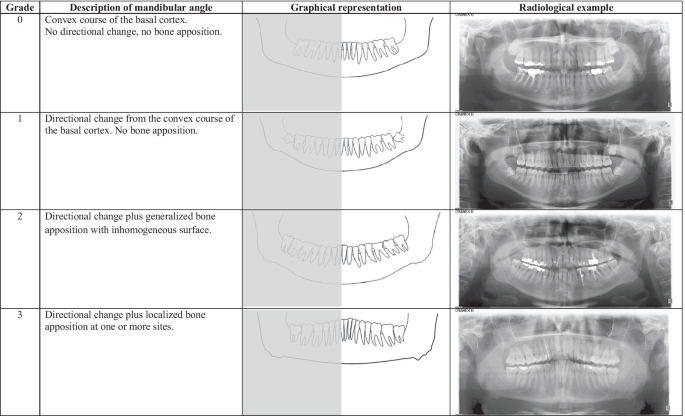

12903 2021 1804 Fig1 HTML